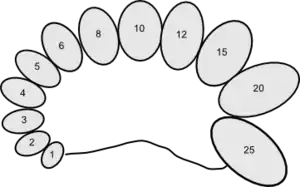

The orchidometer was introduced in 1966 by Swiss pediatric endocrinologist Andrea Prader of the University of Zurich.[1] It consists of a string of twelve numbered wooden or plastic beads of increasing size from about 1 to 25 millilitres. Doctors sometimes informally refer to them as "Prader's balls", "the medical worry beads", or the "endocrine rosary".[2]

The beads are compared with the testicles of the patient, and the volume is read off the bead which matches most closely in size. Prepubertal sizes are 1–3 ml, pubertal sizes are considered 4 ml and up and adult sizes are 15-25 ml.[3]